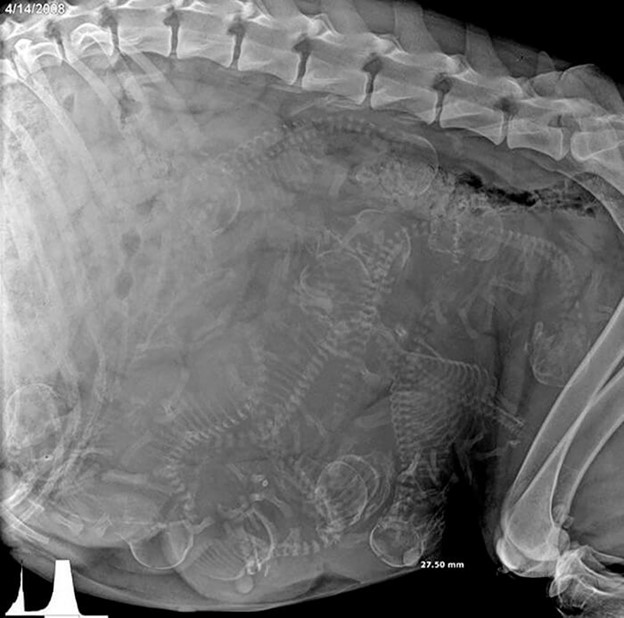

Many Skeletons Inside One Body

You are looking at a large body, and there are many skeletons inside it as you can see the bones. Yes, this is perfectly normal because this is what a dog ultrasound looks like. Everyone is used to looking at human ultrasounds, but this one is bizarre and unique at the same time.

These skeletons are of the little pups hiding inside the womb of their mother. We hope this pregnancy goes well and the dog delivers healthy puppies in no time. We don’t know about you, but we would love to see more of such ultrasounds of various animals.